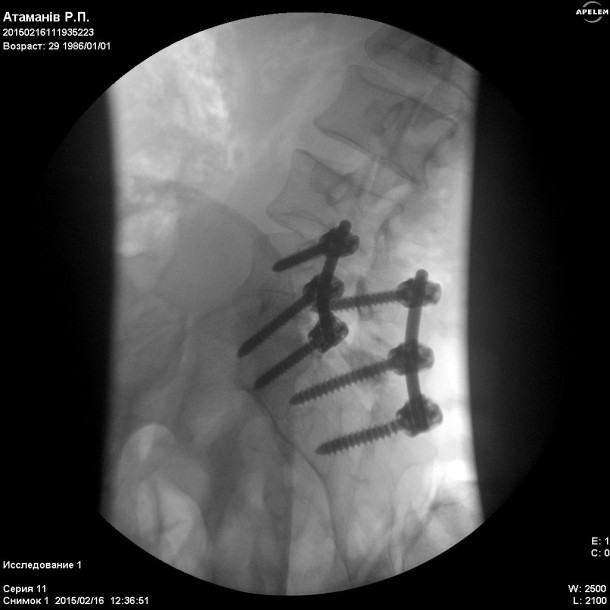

В Харківському державному інституті патології хребта і суглобів Ім. Проф. М. І. Сітенка, Сергію зробили операцію відкритого вправлення Л5 хребця. Та провели стабілізацію на рівні Л4, Л5-С1, конструкцією «медтронік». Тобто йому зафіксували хребет за допомогою металевих з’єднань, – повідомляє БУГ.

На операцію витратили 100 000 гривень. Але, на жаль, конструкція не витримала навантаження хребта і ситуація значно погіршилась. Хлопець прикований до ліжка. Кожен може допомогти йому побороти хворобу. Нині потрібна повторна операція, на яку необхідно зібрати ще 100 000 гривень до кінця березня. Батьки вичерпали всі свої збереження, і самі справитись з цим горем не в стилі. Вони благають про допомогу небайдужих. Батько Сергія захищає нас в АТО від окупації ворогів. Мати має 3-тю групу інвалідності, поліартрит. Тому зібрати потрібну кількість грошей не вдається.